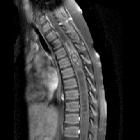

Like other types of astrocytoma, pilocytic astrocytomas typically have an eccentric location within the spinal cord. The most common location is the dorsal portion of the spinal cord .

Fusiform enlargement of the spinal cord is typically seen. Unlike higher grade astrocytomas, pilocytic astrocytomas are almost always well-defined and tend to displace rather than infiltrate the cord .

Associated cysts and syringomyelia are particularly common with pilocytic astrocytomas . Like other types of spinal astrocytoma, hemorrhage is uncommon . Surrounding vasogenic edema is rarely present .

Typical signal characteristics:

- T1: isointense to hypointense

- T2: hyperintense

- T1 C+ (Gd): most enhance but to a lesser degree compared to intracranial pilocytic astrocytomas. The pattern of contrast enhancement is variable

In larger tumors, signal intensity might be heterogeneous due to the intermixture of solid and cystic tumor parts .